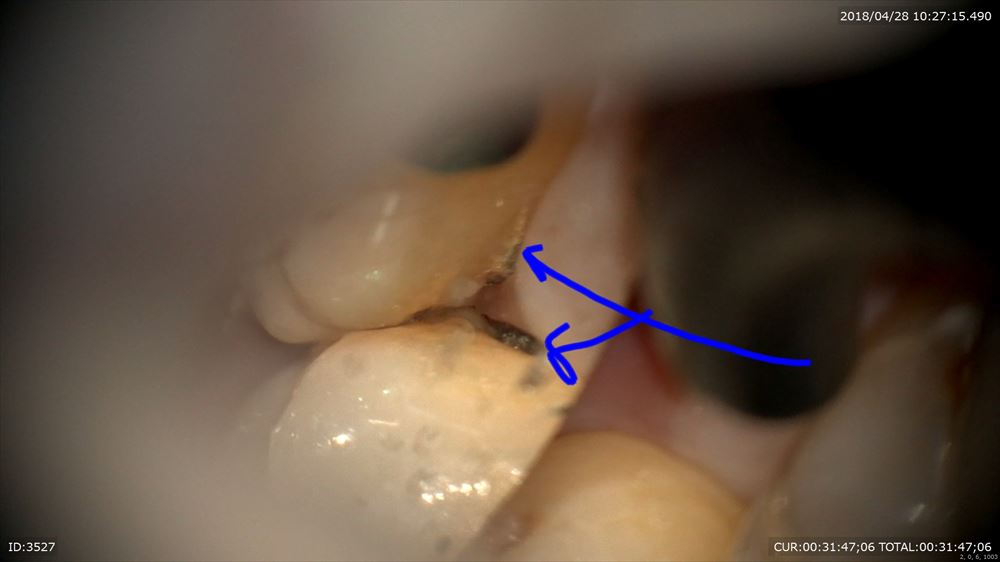

こんにちは。今日は歯周病患者さまの無痛デブライドメントを行いました。マイクロスコープで行うとこんな風に見えます。

私が自らデブライドメントを行うのは下記のような虫歯やクラックを見つけその方の情報をここでも採取しているから。

虫歯見つけた!!

ここは6mmのポケット。必ずほら「歯石(細菌)」が付着。